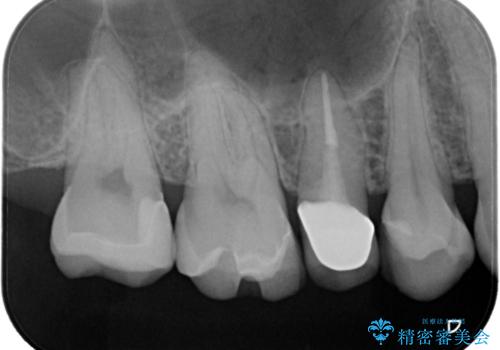

【セラミックインレー】虫歯の治療

- 虫歯を認めたため、セラミックインレーにて治療を行いました。

見た目も綺麗に修復することができ患者様には満足していただきました。

セラミックインレーの接着には必ずラバーダム防湿を行なっています。